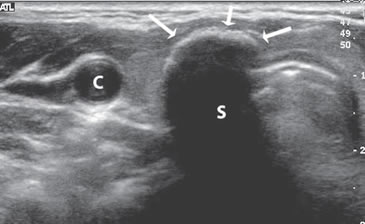

Figura 9. Cáncer papilar, de forma redondeada, de 30 mm de diámetro,

hipoecogénico, con microcalcificaciones periféricas y discontinuas

(flechas). En el aspecto posterior las microcalcificaciones

forman un contorno lineal (flecha abierta).

El patrón de calcificación periférica anular se consideró alguna vez que representaba un hallazgo benigno, pero un estudio demostró asociación con malignidad en 18,5% de los casos17. En ese estudio hubo una tendencia hacia un mayor riesgo de malignidad si el patrón periférico de calcificación era discontinuo (Figura 9) y un menor riesgo de malignidad si el patrón periférico de calcificación era liso y curvilíneo, en forma de cáscara de huevo (Figura 10).

De todos los signos ecográficos asociados a malignidad, las microcalcificaciones es el más específico (85-95%). La presencia de microcalcificaciones en un nódulo predominantemente sólido aumenta el riesgo de cáncer en tres veces y la presencia de calcificaciones gruesas aumenta el riesgo de cáncer en dos veces. El valor predictivo de las microcalcificaciones varía entre 42% a 94% y la sensibilidad entre 26% a 59%5.